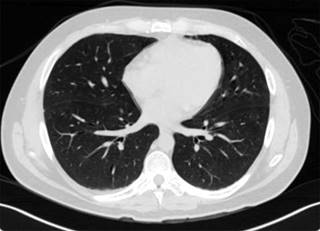

Al cuarto día pasó a la Unidad de Terapia Intermedia para continuar con vigilancia manteniéndose hemodinámicamente estable sin datos de dificultad respiratoria. El control tomográfico del día 02 agosto (Figura 3), mostró algunos datos de vidrio despulido, sugestivos de neumonitis, siendo más evidente en la língula, lo que demostró mejoría franca en relación a estudio previo de ingreso. Se realizó estudio de DLCO2 el cual se reportó con patrón restrictivo leve sin alteraciones a la difusión de CO2.